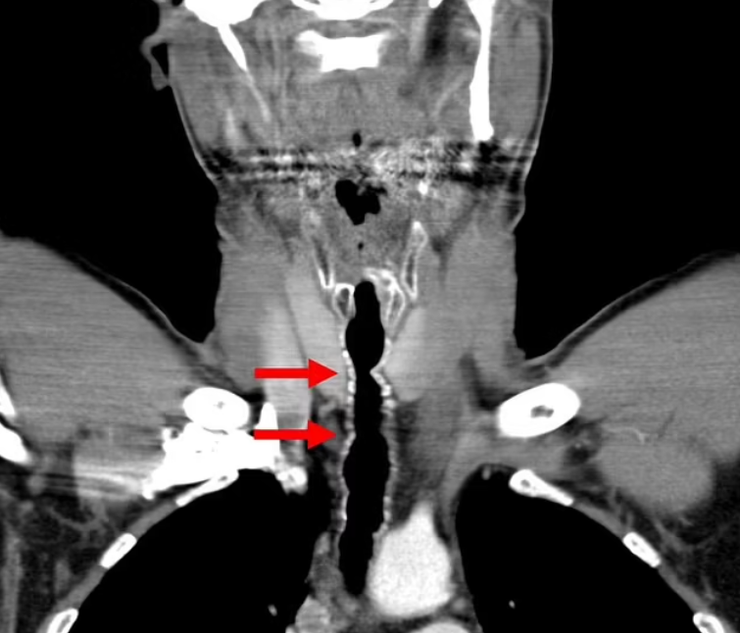

Пацієнт звернувся до лікарів зі скаргами на хрипкий голос, утруднене дихання та хронічний кашель. Його відразу відправили на спеціальну процедуру, аби провести маленьку камеру по дихальних шляхах. Таким чином вдалось виявили кілька волосків, що росли з тієї ділянки горла, де чоловікові колись робили операцію (пересаджували шкіру з вуха).

Лікарі виявили кілька волосків, що росли з тієї ділянки горла, де чоловікові колись робили операцію

Фото: Daily Mail